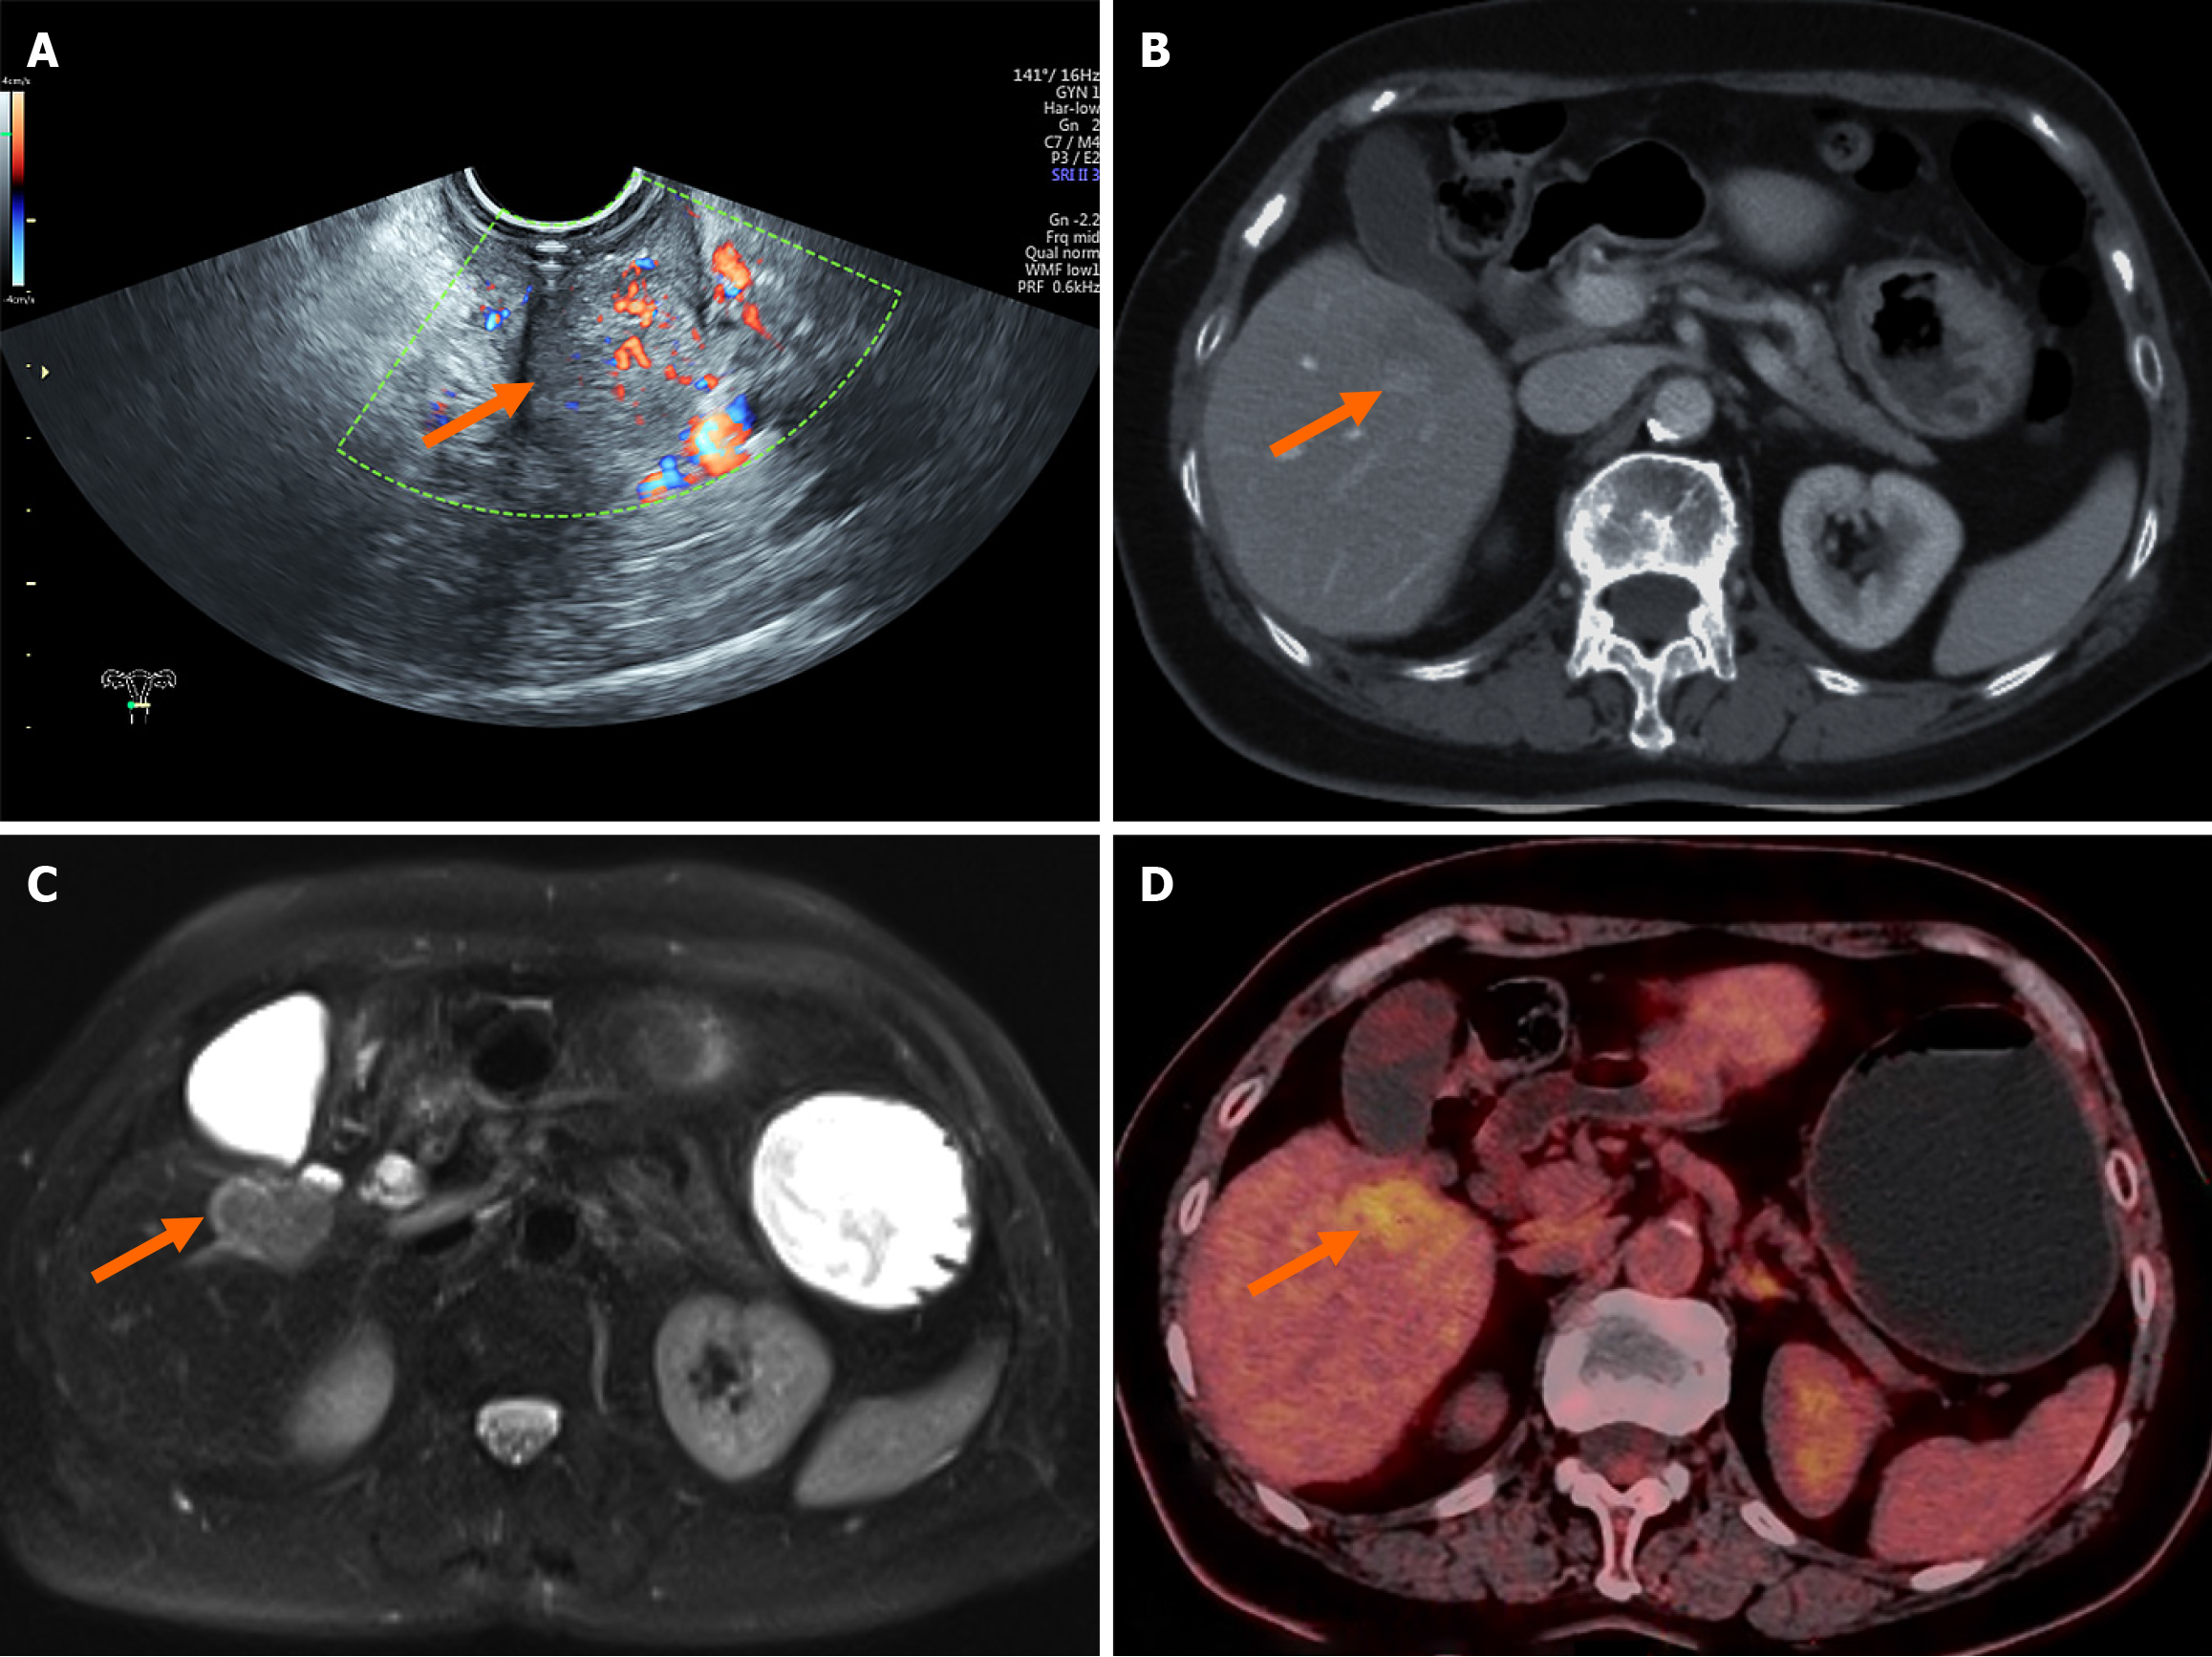

Transvaginal ultrasound confirmed the presence of a solid cervical mass (Figure 2A). Abdominal contrast-enhanced computed tomography (CT) revealed cervical thickening with enhancement and a low-density lesion in the right hepatic lobe (Figure 2B). Liver magnetic resonance imaging revealed a malignant lesion in segment V (Figure 2C), with a differential diagnosis that included primary hepatic malignancy vs metastatic disease. Contrast-enhanced ultrasound of the liver lesion revealed a rapid-in, rapid-out enhancement pattern, favoring a primary liver tumor. Positron emission tomography/CT imaging revealed increased fluorodeoxyglucose uptake in both the cervical lesion and a low-density hepatic mass in segment V (Figure 2D); however, positron emission tomography/CT was unable to definitively differentiate between benign and malignant etiologies.